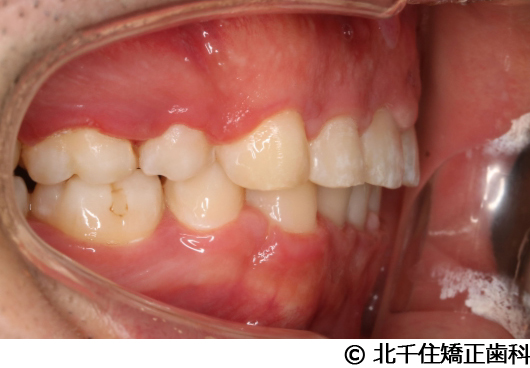

【症例4】下顎前突

- 治療前

- 治療後

- 治療名

- 下顎前突

- 費用

- 1,226,000円(税込)

- 期間

- 2年10ヵ月

- 治療回数

- 32回

- 通院頻度

- 1ヵ月ごと

- 年齢・性別

- 28歳5ヵ月・女性(初診時)

治療内容

-

患者様の症状

主訴:デコボコ、笑顔のとき歯がきれいに見えるようにしたい

治療方法

骨格性の下顎前突および開咬、上顎第二小臼歯と下顎第一小臼歯4本抜歯してワイヤー矯正(セラミックブラケット)。

治療結果

骨格性下顎前突および開咬に対し、抜歯を併用した矯正治療により歯列および咬合関係の調整を行った症例である。治療後は保定装置を使用し、歯列および咬合の安定維持を目的として定期的な経過観察を行っている。

※治療結果は個人差があります。

治療を行う上での注意点(リスク・副作用)

歯磨き不良に伴うカリエスや歯周病、歯根吸収など。